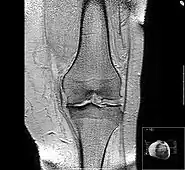

MRI of osteoarthritis in the knee, with characteristic narrowing of the joint space